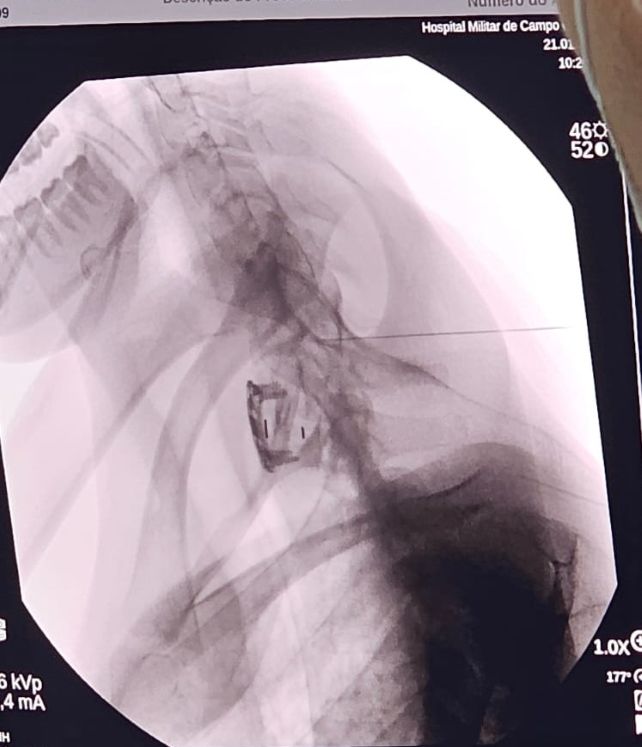

Comandada pelo neurocirurgião Bruno Cortez, do Hospital Souza Aguiar, do Rio de Janeiro, a equipe médica composta por profissionais do HMilACG utilizou um aparelho de radioscopia para visualizar, por meio de raio-x, a introdução da agulha na região lesionada, permitindo assim a infusão da proteína diretamente no tecido medular. O procedimento é considerado pouco invasivo, mas, delicado, exigindo precisão e perícia na execução.